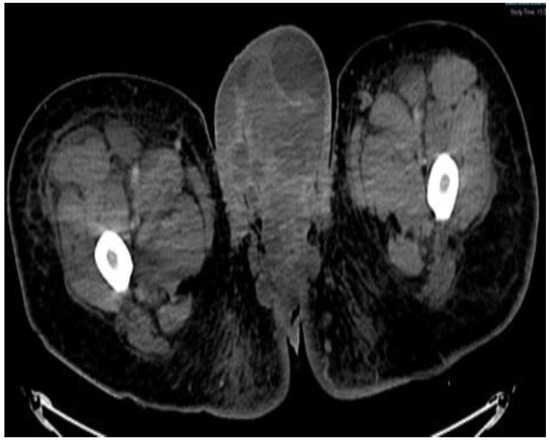

Figure 3.

MRI in the axial view T1 TSE FS PRE showing hyperintense linear non-enhancing structure consistent with ultrasound finding of thrombosed dorsal penile veins.

This plan required alteration, as the patient presented again to the hospital three weeks later with worsening symptoms from persistent priapism. This time he also presented with dyspnea and was found to have undergone rapid disease progression, with imaging evidence of new bilateral lung metastases, hepatic metastases, pelvic and inguinal adenopathy, and pubic bone lytic lesions. He was also found to have developed multiple venous thromboemboli with a high clot burden, including bilateral subsegmental pulmonary emboli and thromboses of the right external iliac, left greater saphenous, and bilateral dorsal penile veins (Figure 3, Figure 4, Figure 5, Figure 6, Figure 7, Figure 8 and Figure 9). In addition, there was increased spiculated soft tissue swelling along the dorsal penile shaft and extensive nodularity in the scrotum and inguinal lymph nodes, suggesting tumour invasion of the reproductive organs (Figure 4, Figure 5 and Figure 6). During the physical examination, the penis, scrotum, and pre-pubic areas were dramatically enlarged and firm, with numerous cutaneous lesions consistent with replacement with a tumour. Urology staff were consulted, and they suggested that the disease was not resectable.